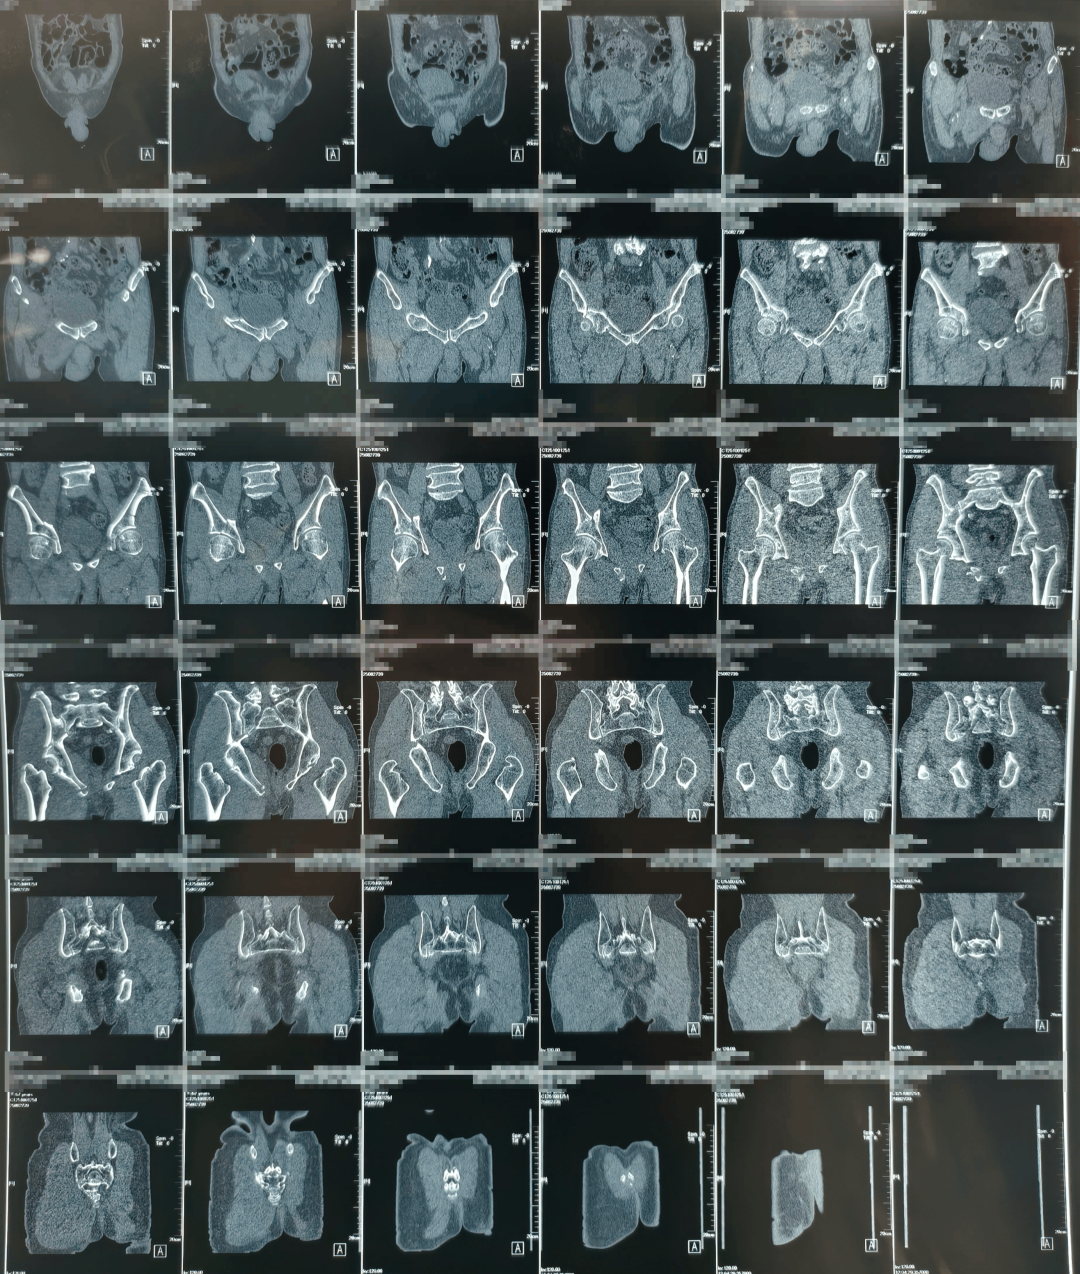

术前

团队通过三维影像重建,为患者量身定制手术路径,数据导入系统后生成个性化复位方案。

点击查看大图